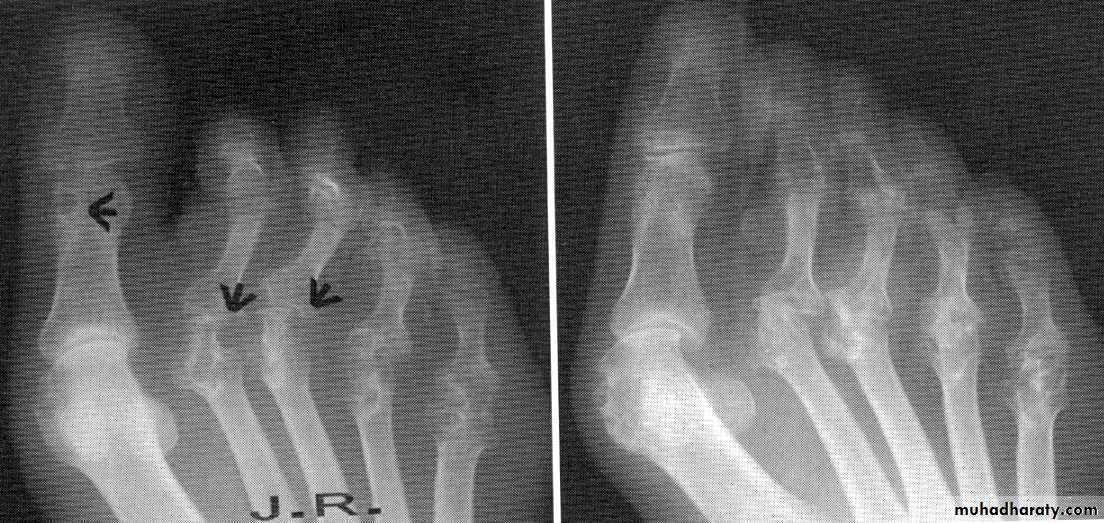

3- X-ray: the typical radiographic changes of RA are periarticular osteopenia& marginal non proliferative erosions.

Tendon and bursa involvement are frequent and often clinically dominant in the early disease. RA can affect any joint, but has a predilection for metacarpophalangeal, proximal interphalangeal and metatarsophalangeal joints, as well as the wrists and knees.Articular and periarticular manifestations include joint swelling and tenderness to palpation ,with morning stiffness and sever motion impairment in the involved joints.

Provide a good reflection of disease activity. The typical features are symmetrical swelling of MCP& PIP joints. They are hot, tender & have stress pain on passive movement.Specific hand abnormalities include swan neck deformity, button hole (boutonnière) deformity& Z- deformity of thumb. Other abnormalities include :

dorsal subluxation of ulnar styloid of the wrist , trigger finger, cock up deformity of the toe, flatfoot, Baker's(popliteal) cyst which can be mistaken for DVT, but past history of joint disease & Doppler U/S can establish the diagnosis of DVT.